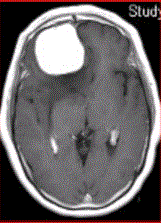

问题 女,64岁,发作性意识丧失,左侧肢体无力,MR显示右侧额叶等T1信号影(下图),病变明显强化,最可能的诊断是

选项 A.室管膜瘤 B.星形细胞瘤 C.脊索瘤 D.脑膜瘤 E.转移瘤

答案 D